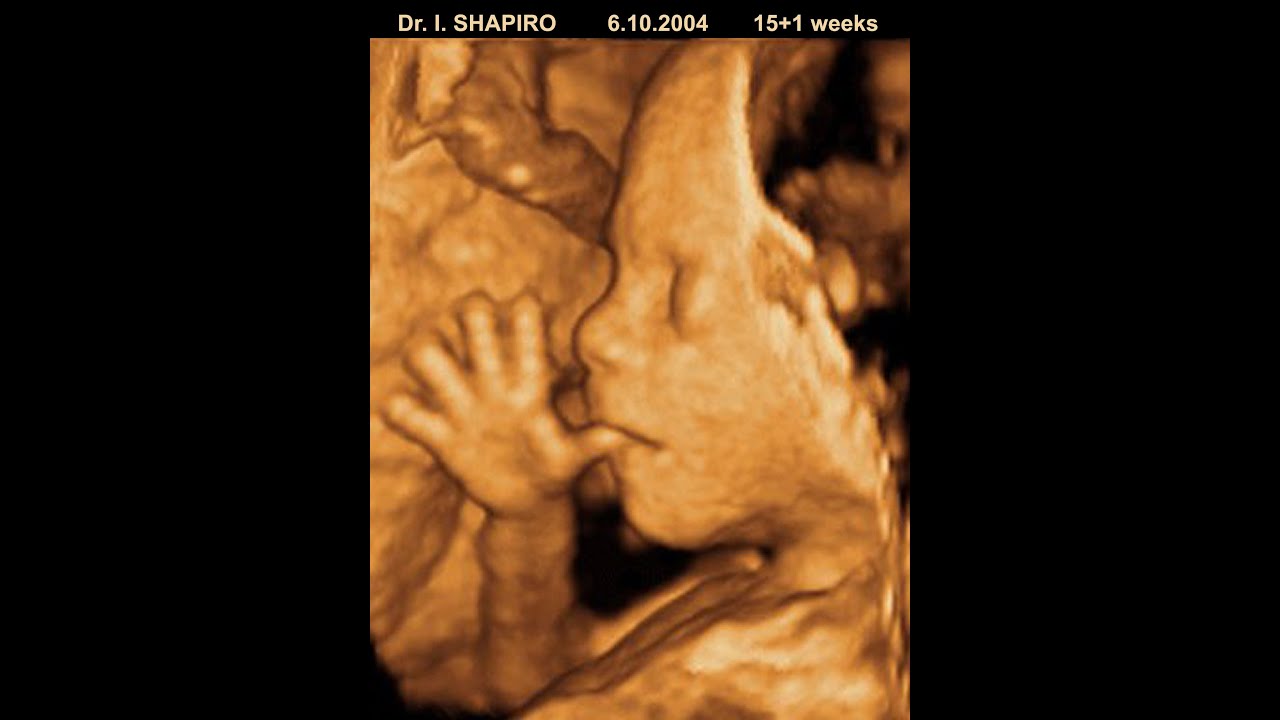

DMS 333 Obstetrics I